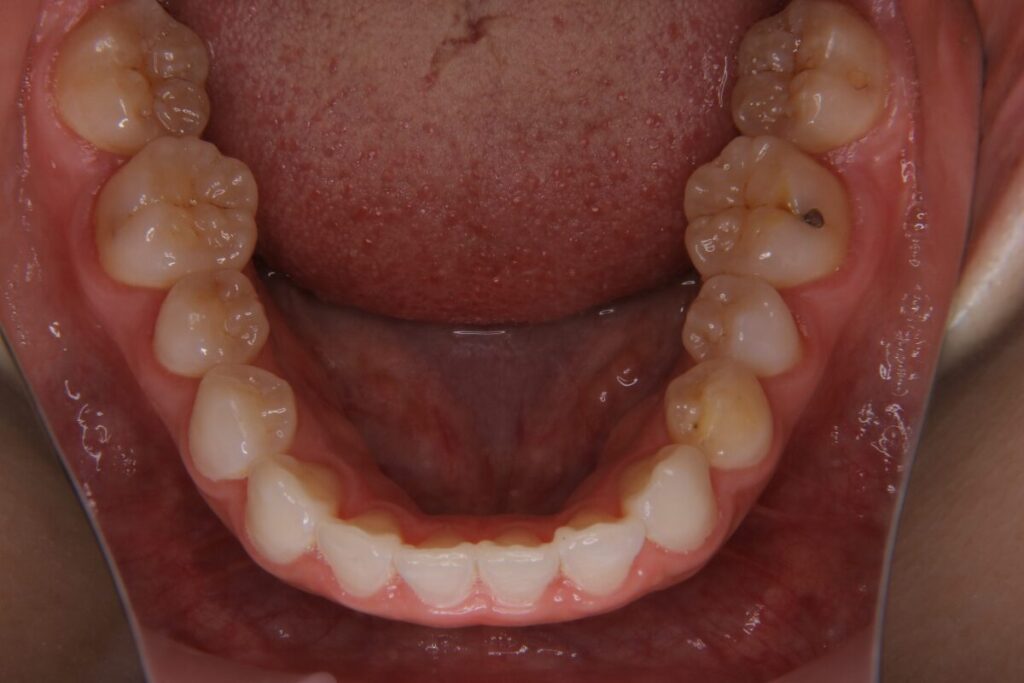

| 患者 | 40歳女性 |

|---|---|

| 主訴 | ガタガタ、噛めない |

| 診断名 | 叢生を伴う骨格性下顎後退 |

| 治療内容 | マウスピース型矯正装置(インビザライン) |

| 抜歯の有無 | 非抜歯 |

| 治療期間 | 9か月 |

| 費用(税込) | 627,000円 |

| リスクと副作用 | 痛み等、歯根吸収/歯肉退縮、後戻り、むし歯・歯肉炎の可能性。 |

【医師コメント】

15年ほど前に矯正治療を受けられていた方で、後戻りによる再治療のご相談でした。

精密検査の結果、骨格的な問題は少なく、噛み合わせの基盤も大きく崩れていなかったため、部分矯正での対応が可能と判断しました。

インビザラインを19枚+追加分で治療を行い、9か月で完了。前歯のねじれや重なりが整い、奥歯も起き上がったことで、噛み合わせが安定しました。